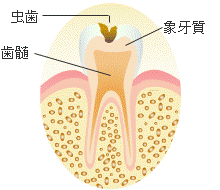

虫歯がエナメル質を超えて、その下の象牙質にまで及ぶと、病変は急速に広がって行きます。

象牙質はエナメル質と違って、それほど硬くないためです。

そのため、表面では小さな穴でしか無くても、奥ではとても大きなものになっている場合が多いのです。

また、進行した虫歯が歯髄(歯の神経)に近づくにしたがって、甘い物を食べると痛みを感じたり、冷たい空気や水がしみたりするといった自覚症状が現れて来ます。